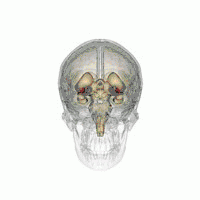

Deep brain stimulation

DBS-probes shown in X-ray of the skull (white areas around maxilla and mandible represent metal dentures and are unrelated to DBS devices)